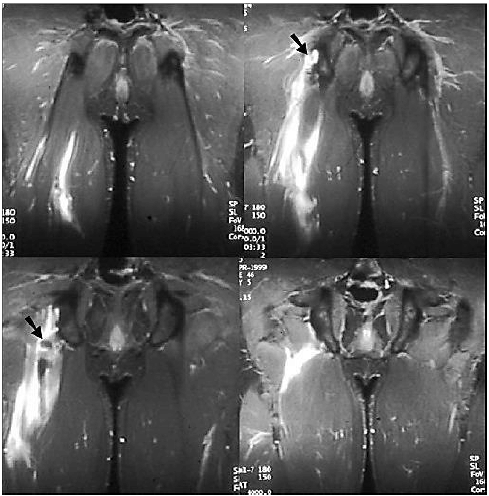

Atualmente, a RM vem sendo cada vez mais solicitada para o estudo das patologias osteoarticulares, sendo capaz de demonstrar anomalias ósseas como osteomielite e processos infiltrativos da medula óssea mais precocemente do que os demais métodos de imagem, mostrando-se, ainda, bastante superior à radiologia convencional e à TC no estudo das anomalias de partes moles, graças à sua excelente resolução de contraste.

Observe a imagem e assinale a alternativa correspondente.